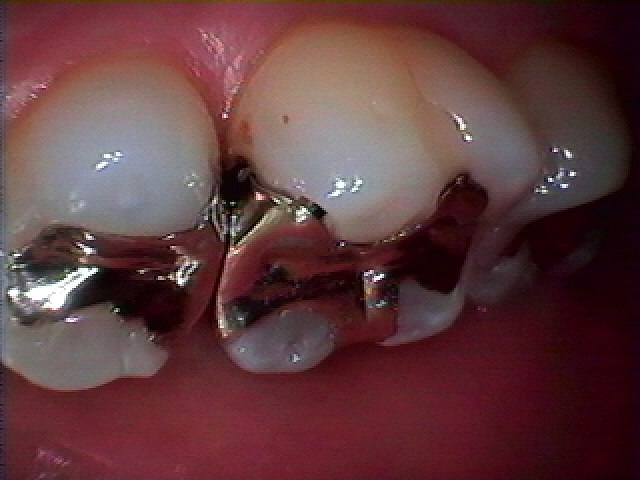

右上5,6番の銀歯をはずして虫歯治療をおこなっていきます|お知らせ |広島市安佐南区の歯科医院 右上5,6番の銀歯をはずして虫歯治療をおこなっていきます トップ お知らせ・ブログ お知らせ 右上5,6番の銀歯をはずして虫歯治療をおこなっていきます 右上5,6番の銀歯をはずして虫歯治療をおこなっていきます この銀歯の下に虫歯が存在しています 銀歯も適合が悪くなっています 中はこのように大きく虫歯になっています 中の虫歯を除去して行きます 神経に気を付けながらこのように虫歯を除去しています セレックセラミックにてきれいに修復しています きれいに仕上がりました 本来の歯の輝きが戻りました Web診療予約 初めての方へ 選ばれ続ける理由 院内設備について 歯が痛いしみる一般歯科 歯がぐらぐらする歯周病 健康な歯を保ちたい予防歯科 子供の虫歯予防をしたい小児歯科 銀歯をセラミックに審美歯科 白い歯を目指しませんか?ホワイトニング 矯正専門医がいるので安心矯正歯科 抜けた歯を補いたいインプラント・入れ歯 医院案内 スタッフ紹介 メリィハウス歯科クリニックオフィシャルホームページ ラベンダー歯科クリニックオフィシャルホームページ お知らせ・ブログ ホーム 診療科目 一般歯科 歯周病治療 予防治療 小児歯科 審美治療 ホワイトニング 矯正歯科 入れ歯・インプラント マウスピース矯正 初めての方へ 院長・スタッフ 設備紹介 医院案内・アクセス メニューを閉じる